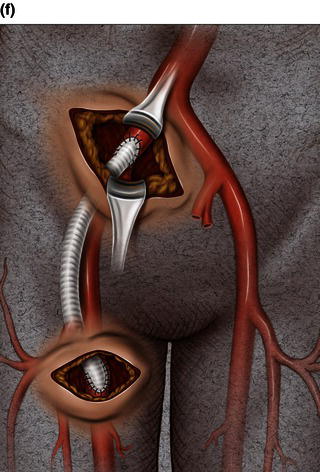

A 15 cm semi-lunar right flank incision is made four finger-breaths above the groin crease. Division of the external oblique, internal oblique and transversus abdominus muscles is performed in the direction of their fibers. The extraperitoneal fascia and peritoneum are then retracted medially and dissection is carried out in the avascular plane of the retroperitoneum down to the level of the psoas muscle. All of the abdominal contents are then retracted medially with the help of a handheld retractor or an Omni retractor, providing excellent exposure of the lower infrarenal aorta, common iliac artery, and iliac bifurcation. The right common iliac artery along with the hypogastric and the external iliac artery are identified and mobilized (Fig. 1.14a). Care is taken to spare the right urether which crosses the common iliac artery before diving deep into the pelvis. A Rummel tourniquet is applied to control the proximal common iliac artery, the external iliac artery, and origin of the hypogastric artery; alternatively, vascular clamps could be applied for control. Heparin is usually given to the patient prior to clamping the vessels. An arteriotomy is made on the common iliac artery with a no. 11 blade and extended with Pott’s scissors close to the bifurcation of the hypogastric artery and the external iliac artery. A 10 mm conduit is then sewn in an end-to-side fashion using 5-0 prolene sutures (Fig. 1.14b). The 10 mm graft is subsequently tunneled through the retroperitoneal space beneath the inguinal ligament and brought out through the groin incision used to expose the common femoral artery. The graft is subsequently flashed and clamped at the groin incision with the Rummel tourniquets released from the common iliac artery, external iliac artery, and hypogastric artery. The 10 mm conduit is subsequently looped with a Rummel tourniquet and ready to be punctured with an 18 gauge needle for access and introduction of a guide wire and an introducer sheath (Fig. 1.14c). The introducer sheath is subsequently exchanged for a device sheath, which is advanced into the distal aorta (Fig. 1.14d). The endoluminal graft is then introduced into the delivery sheath and deployed to the target area. Wires and sheaths are removed from the 10 mm conduit and the conduit is clamped.

The conduit can either be trimmed to the appropriate length and the conduit tied off as a stump (Fig. 1.14e) or the distal end of the conduit can be sewn to the more distal iliac system in an end-to-end fashion as an interposition graft. Or, more commonly, the conduit can be brought to the groin by tunneling the conduit under the inguinal ligament and performing either an end-to-end anastomosis or an ilio-femoral conduit. The ilio-femoral conduit is performed by making an arteriotomy on the adequately exposed common femoral artery after adequate proximal and distal control is achieved. An end-to-side anastomosis is constructed with a 5-0 prolene suture with adequate flushing maneuvers performed prior to completion of the anastomosis (Fig. 1.14f). The ilio-femoral conduit is best for patients who may require further intervention for diffuse thoracic aneurysmal disease as the conduit may be reused through a simple infrainguinal incision in the future. The groin incision is approximated in layers. The right flank incision is irrigated, a 10 Fr Jackson–Pratt drain is placed in the retroperitoneal space and the incision closed in layers. The same technique can be applied to the infrarenal aorta and thoracic aorta. Similarly, end-to-side grafting of a conduit to the axillary artery, as described elsewhere, to facilitate deep hypothermic circulatory arrest also provides excellent access to the thoracic aorta via the innominate [2].

Fig. 1.14 (a) Retroperitoneal exposure. (b) A 10 mm conduit sewn to the iliac artery. (c) Conduit brought out of the incision with cannulation of the conduit with an introducer sheath. (d) Introducer sheath exchanged for a device sheath and advanced through the 10 mm conduit to the distal abdominal aorta. (e) Ligation of a 10 mm conduit. (f) Conduit tunneled and sewn to the femoral artery as an ilio-femoral conduit.